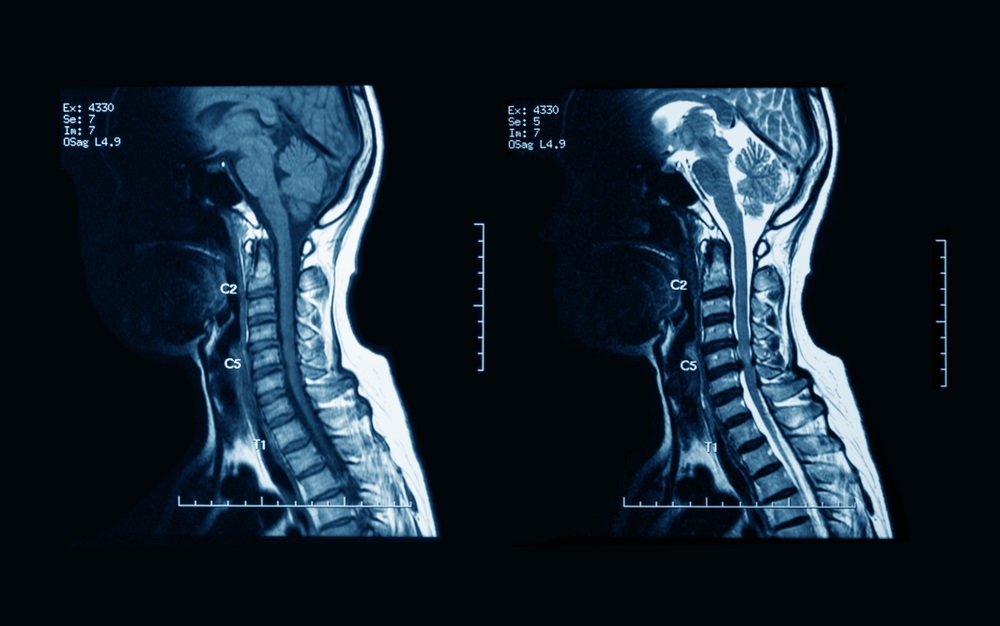

Narrowing of Spinal Cord

Also known as spinal stenosis, this condition involves the narrowing of the spinal canal, causing pressure on the spinal cord and nerves. Through precise diagnostics and personalized care, we aim to alleviate symptoms and improve spinal functionality, often utilizing a combination of surgical and non-surgical approaches.